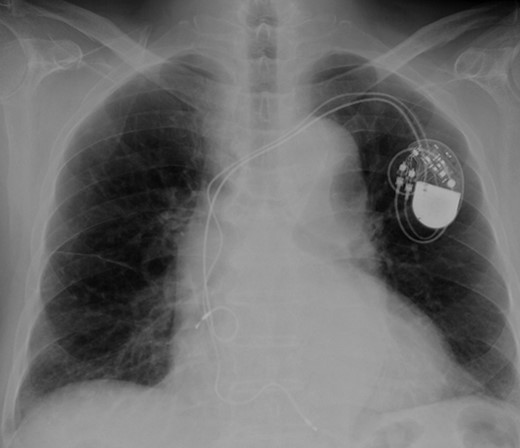

According to the current guideline for pacemaker infection, it was decided to remove the whole pacemaker system, including the two leads. Since implantation of new transvenous leads seemed undesirable because of ongoing active endocarditis, it was decided to implant epicardial leads on the left atrium and left ventricle via a left mini thoracotomy. Because the patient had complete AV block without any spontaneous R wave, a new DDD pacemaker system was implanted first. The atrial lead was implanted on the appendage of the left atrium, and the ventricular lead was implanted onto the lateral wall of the left ventricle near the first obtuse marginal branch (Fig. 3). The old infected pacemaker system was then explanted by percutaneous extraction.

After the operation, the patient recovered rapidly. Of note, postoperative transthoracic echocardiography showed dramatically improved LV function, with EF of 56%. Moreover, dyssynchrony disappeared. On the other hand, the vegetation at the tricuspid valve remained unchanged. He was transferred to a territorial hospital for further therapy with antibiotics on the seventh postoperative day. Now, 3 years after surgery, the patient is doing very well without any sign of heart failure.